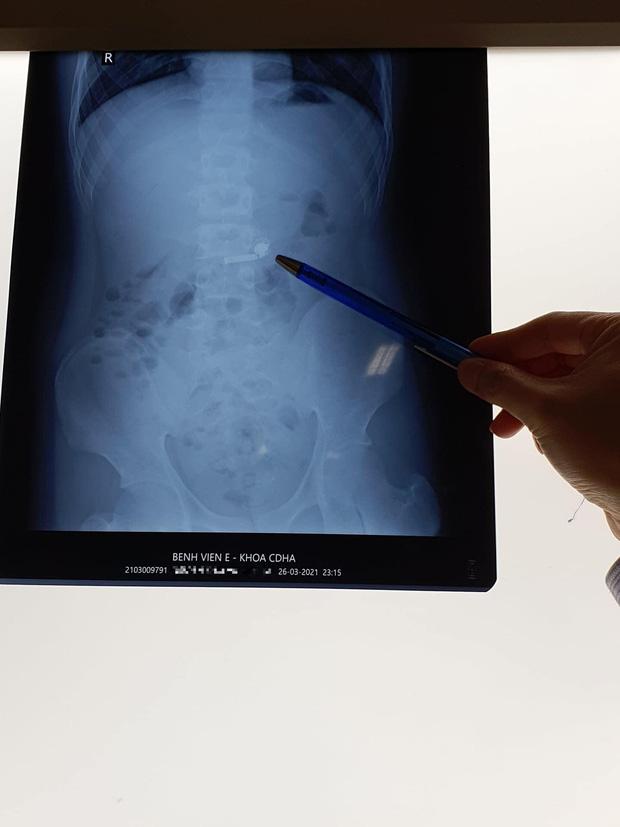

Các bác sĩ chỉ định bệnh nhi làm các xét nghiệm và chiếu chụp cần thiết. Kết quả chụp X-quang cho thấy, trong ổ bụng bệnh nhi có hình tai nghe điện thoại không dây. Tuy nhiên, do người bệnh có tiền sử mắc bệnh tự kỷ từ bé nên việc điều trị không dễ dàng.

Kết quả chụp X-quang cho thấy, trong ổ bụng bệnh nhi có hình tai nghe điện thoại không dây

Dị vật đã trôi xuống dạ dày